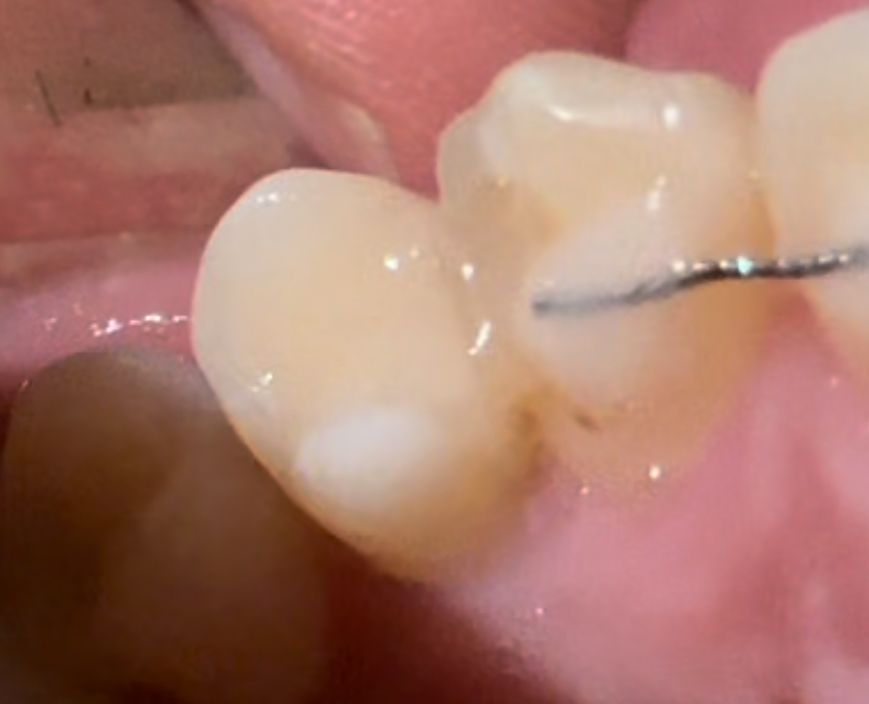

레진 안에 충치가 생긴건가요? 다 같은 송곳니 입니다 마지막 진료는 작년 12월이었습니다

혹시 레진 안에 충치가 생긴건가요? 사진은 다 하나의 송곳니 입니다 핸드폰 라이트를 비추면 검은색이 잘 안보이고 라이트를 끄면 잘보이는 거 같아요

• 1번 째 사진

• 안녕하세요 치과의사 김철진입니다. 정확한건 엑스레이를 찍어보셔야될것같습니다. 육안상으로는 안쪽에 변색 또는 충치가 생긴거 같습니다.

1. 레진 하방으로 이차충치가 생길 가능성도 있긴 합니다.

2. 다만, 지금 사진상에서 나타나는 투명도 차이는 레진 재료 자체의 특성일 수도 있습니다.

3. 충치의 증상 (통증, 시림)이 있다면 치과를 내원하여 엑스레이 사진을 찍어보시면 되겠습니다.